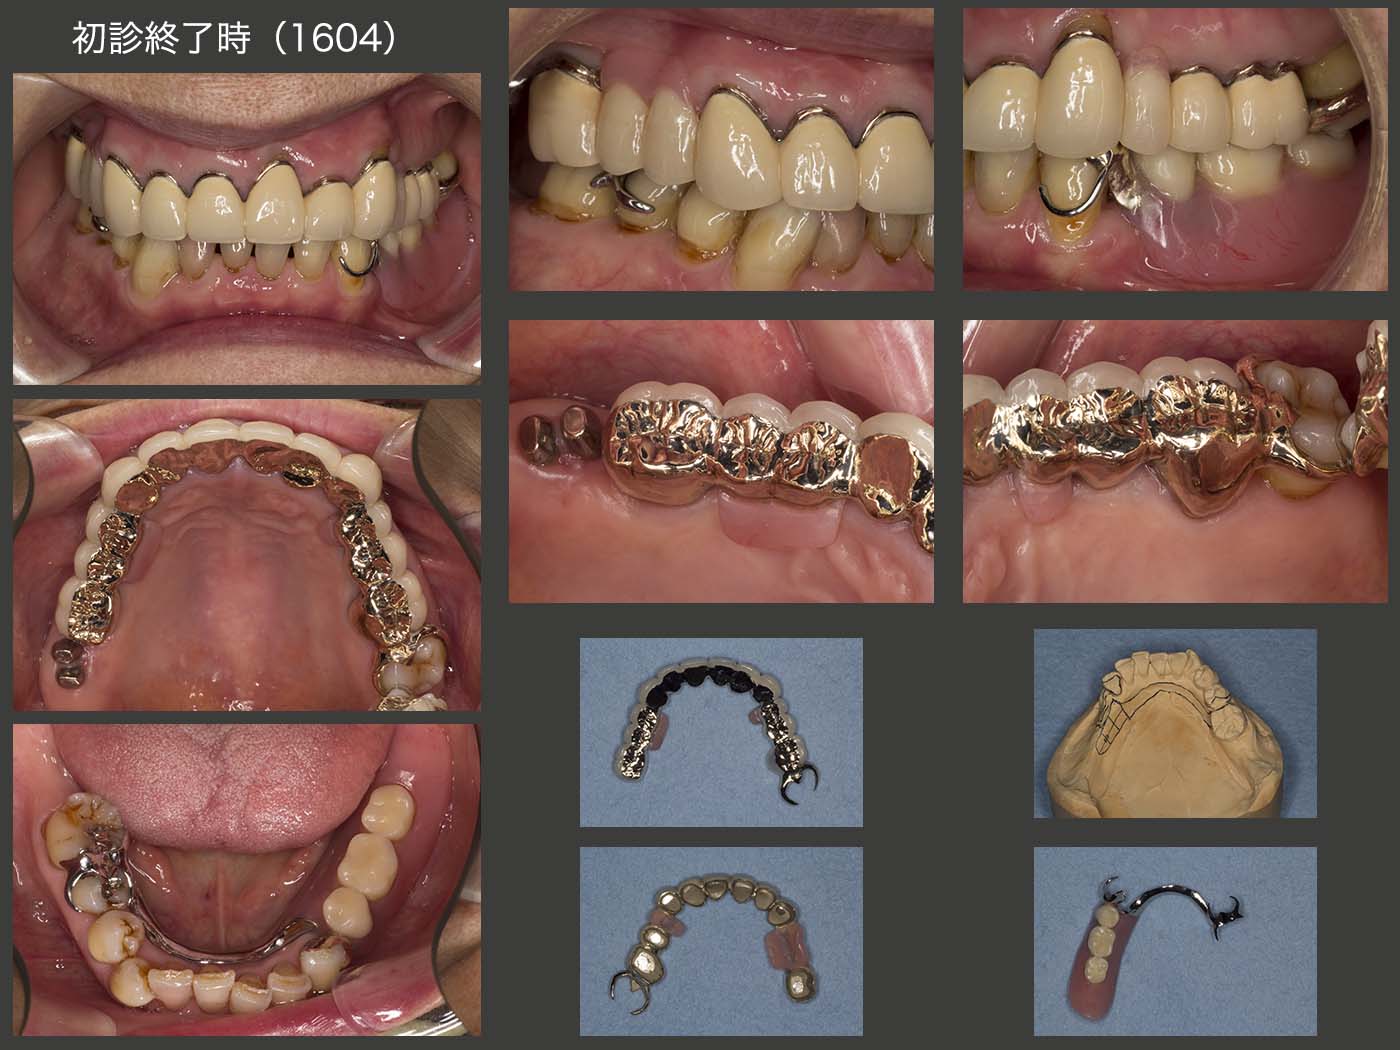

2015年6月,ほぼ全ての基礎治療が終了した状態.移植歯も特に問題なく機能している.上顎は条件の悪い歯が多いため,将来の変化に対応しやすいコーヌス義歯を選択することにした.下顎は,暫間義歯で特に問題がなかったため,この形を踏襲し,大連結装置に強度を保たせた金属床義歯を製作することにした.

2016年4月,初診終了時の状態.移植歯の歯周ポケットは頰側で5mm認められた.水平的動揺も若干あり,将来が心配な状況であった.左上6の遠心は初診時8mm,初診終了時にも6mm残存してしまった.もちろん,歯根端切除術を施した左右1の予後も心配である.このように,上顎に予後不安な歯が多いが,可撤式義歯なので将来何とか対応できるのではないかという安心感もある.下顎は全ての残存歯が有髄歯なので将来の不安は少ない.

初診終了時,義歯装着時の状態.下顎義歯において,左下3のクラスプのラグと金属床のフレームを近接させ,将来顎堤が吸収し,対合歯が挺出した際に,そこで切断できるよう対応しておいた.(レストの位置でリベースすると,対合歯の挻出分,下顎の人工歯の削去量が大きくなるので,挻出量によってはクラスプを付け替えた方が,調整量が少なくてすむ.しかし今回は,コーヌス義歯で2次固定してあるので,対合歯の挻出は少ないと思われる.)